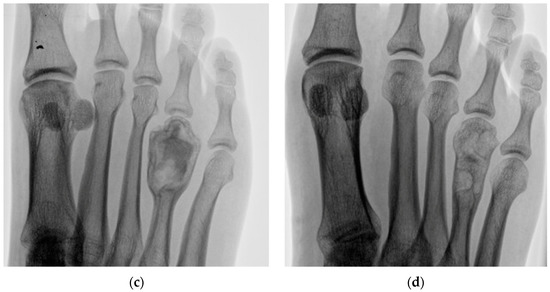

1 | 23 M | 2 | Right foot 4th metatarsal | 20 | Aneurysmal bone cyst | 30 |

4 | 27 F | 2 | Left foot 2nd metatarsal | 24 | Enchondroma | 23 |